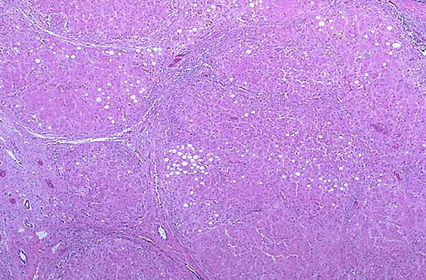

TISSUE TYPE: O.o (loss of architecture) PATHOLOGY: thick fibrous speta with inflamatory cells .. separate nodules of undefined cells. (steatosis) Diagnosis: liver cirrhosis xD KEY: CAN'T SEE ANY SPECIAL THING ABOUT LIVER CAUSE ACTULLAY IT'S DEAD :D